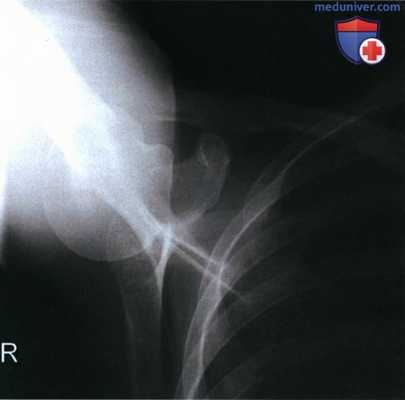

РИСУНОК 3 Рентгенограмма ключицы в ПЗ проекции: перелом. РИСУНОК 4 Рентгенограмма ключицы в аксиальной ПЗ проекции: перелом.

б) Наклон ЦЛ. При рентгенографии ключицы в аксиальной ПЗ проекции краниальный наклон ЦЛ на 15-30° позволяет спроецировать большую часть ключицы выше грудной клетки и оценить степень смещения отломков при наличии перелома. Несмотря на то, что степень наклона в разных медицинских учреждениях может различаться, на всех рентгенограммах ключица будет сдвинута вверх.

Чем больше угол, тем выше будет проецироваться ключица. Поскольку в 80% случаев перелом ключицы происходит в ее средней трети и в 1 5% случаев — в ее латеральной трети, целесообразно ЦЛ наклонять так, чтобы латеральная и средняя трети ключицы визуализировались выше грудной клетки и лопатки. Сравните рентгенограммы на рис 3 и 4 (см. выше) и обратите внимание, как увеличение краниального наклона ЦЛ позволяет спроецировать латеральную и среднюю трети ключицы выше лопатки. На обеих рентгенограммах перелом ключицы очевиден, однако без рентгенограммы в аксиальной ПЗ проекции перелом ключицы без смещения на фоне лопатки можно не заметить.

а) Анализ. Медиальный конец ключицы накладывается на третье ребро. Латеральный конец ключицы визуализируется не выше, а на уровне акромиального отростка. ЦЛ был наклонен недостаточно.